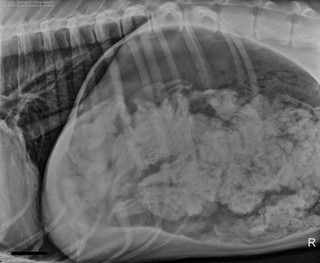

Αυτό που προκαλεί αίσθηση είναι οι ακτινογραφίες από το στομάχι του τετράποδου που δείχνουν το μέγεθος της αταξίας του. Για την ιστορία, ο σκύλος επέστρεψε σώος, μετά την εγχείρηση, πίσω στο σπίτι.